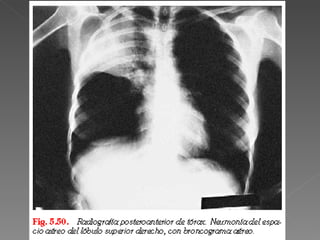

Síntomas: tos productiva, disnea, dolor torácico, fiebre. Si es geronte: confusión y taquipnea. Signos: Estertores crepitantes o soplo tubario. Los signos y síntomas no predicen la etiología, como la comorbilidad.